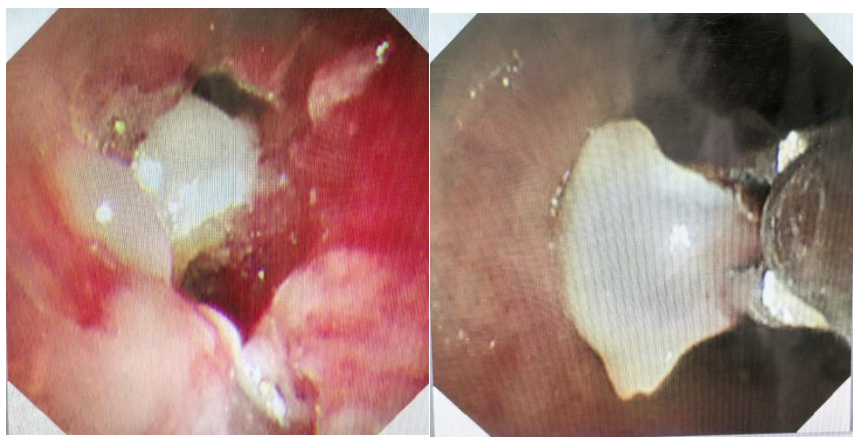

张艳丽、小儿呼吸内科二病区副主任朱志杰熟练操控支气管镜,一切有条不紊、井然有序,镜下可见:脱落的牙齿被增生肉芽紧紧包裹,牢牢嵌顿在左主支气管远端,且不时有脓液从异物下方涌出,团队成员沉着应对,先精准钳除部分肉芽组织,松动异物,最终用异物钳完整取出牙齿。随后,团队为患儿进行肺泡灌洗,清除左肺脓性分泌物,并对增生的肉芽组织实施冷冻治疗。

当支气管镜显示气道通畅、脓液尽除时,在场所有人高悬的心终于落地。在这场“气道保卫战”中,河南省妇幼保健院小儿呼吸内科再次彰显了速度与温度,体现了能力与担当,整个诊疗过程响应迅速,有条不紊,多团队协作,一切为了患者,在短时间为患者解除隐患,获得了家属的高度认可。